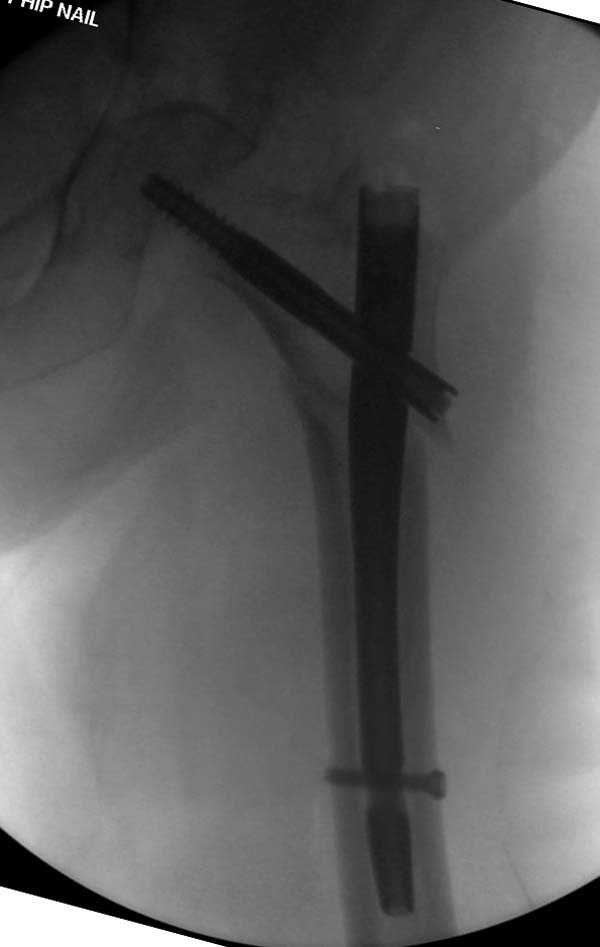

Ошибка при установке Гамма 3

Здесь представлен случай, где в послеоперационном периоде обнаружена техническая ошибка, Gamma 3 установлен с нарушением методики. Больная в 91 лет, прооперирована через день после поступления и выписана через 48 часов.

При первом послеоперационном поликлиническом осмотре больная предъявила жалобы на боли в бедре. В серийных снимках обнаружен продольный перелом верхнего отдела бедра.

Считаем, что техническая ошибка произошла во время установки гвоздя, когда рассверливанию канала не уделили должного внимания. Канал остался узковат, и гвоздь был забит с силой. Полная нагрузка конечности приостановлена на две недели, и боли в конечности изчезли. Больная начала нагрузку и перелом срастается.-- Djoldas Kuldjanov, M.D.Associate ProfessorDepartment of Orthopedic SurgerySt. Louis University